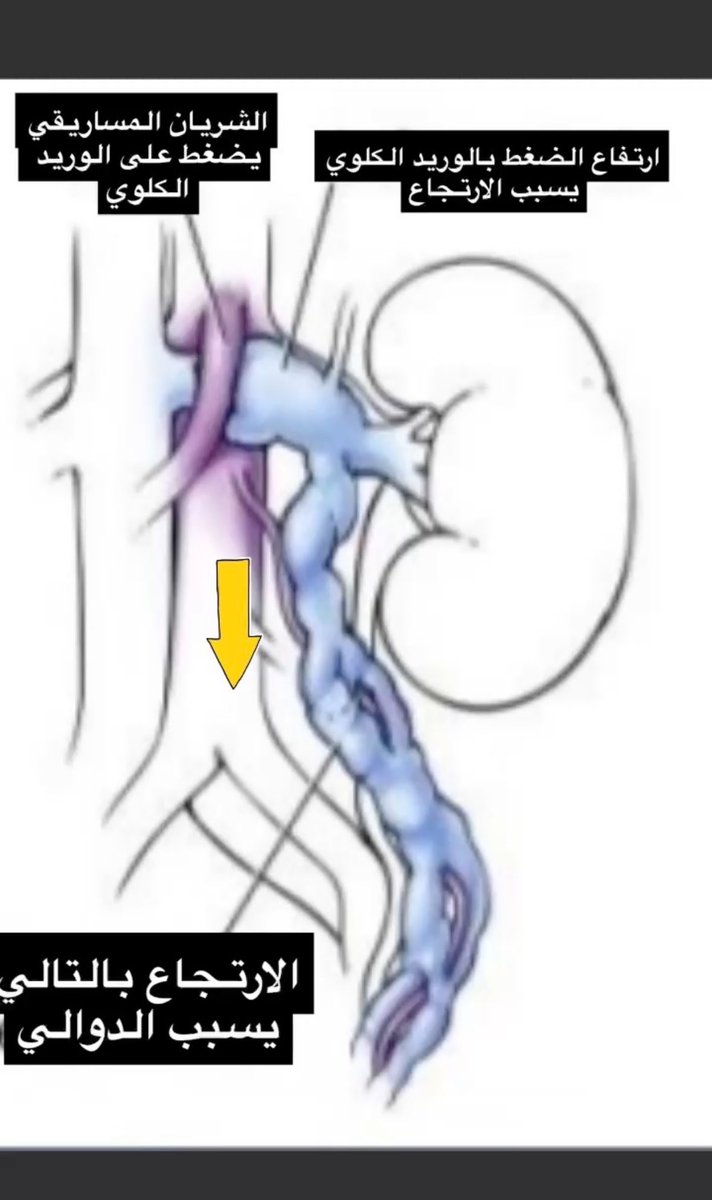

٢- لنفهم فعالية الاجراء يجب ان نفهم السبب الرئيسي وكيفية تكوّن الدوالي أساساً. قلنا بالسابق أن الدوالي عبارة عن أوردة متضخمة. وظيفة الأوردة هي ارجاع الدم إلى القلب. لكن مالذي يمنع ارتجاع الدم الى الاسفل (بفعل الجاذبية) عندما يعود الدم من أسفل الجسم إلى القلب؟ صمامات الأوردة.

٧- هناك اسباب اخرى غير وراثية تؤدي لظهور دوالي الخصية. أهمها متلازمة ضغط الشريان المساريقي على وريد الكلية (متلازمة كسّارة البندق كما بالصورة)، ارتفاع ضغط دم الوريد البابي ، انسدادات لأسباب اخرى وغيرها. كل هذا لا يمكن الكشف عنه جراحياً ولكن يتم التعرف عليه خلال القسطرة.